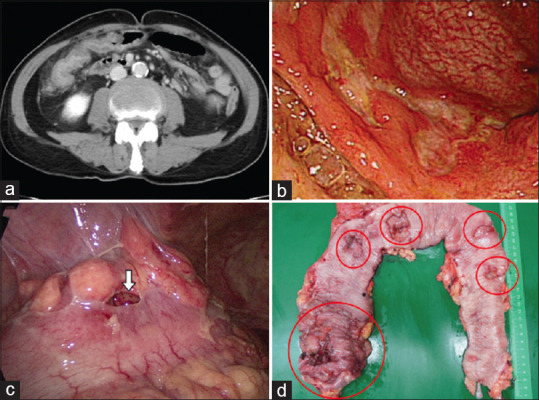

Primary colonic natural-killer T-cell lymphoma mimicking Crohn's disease.